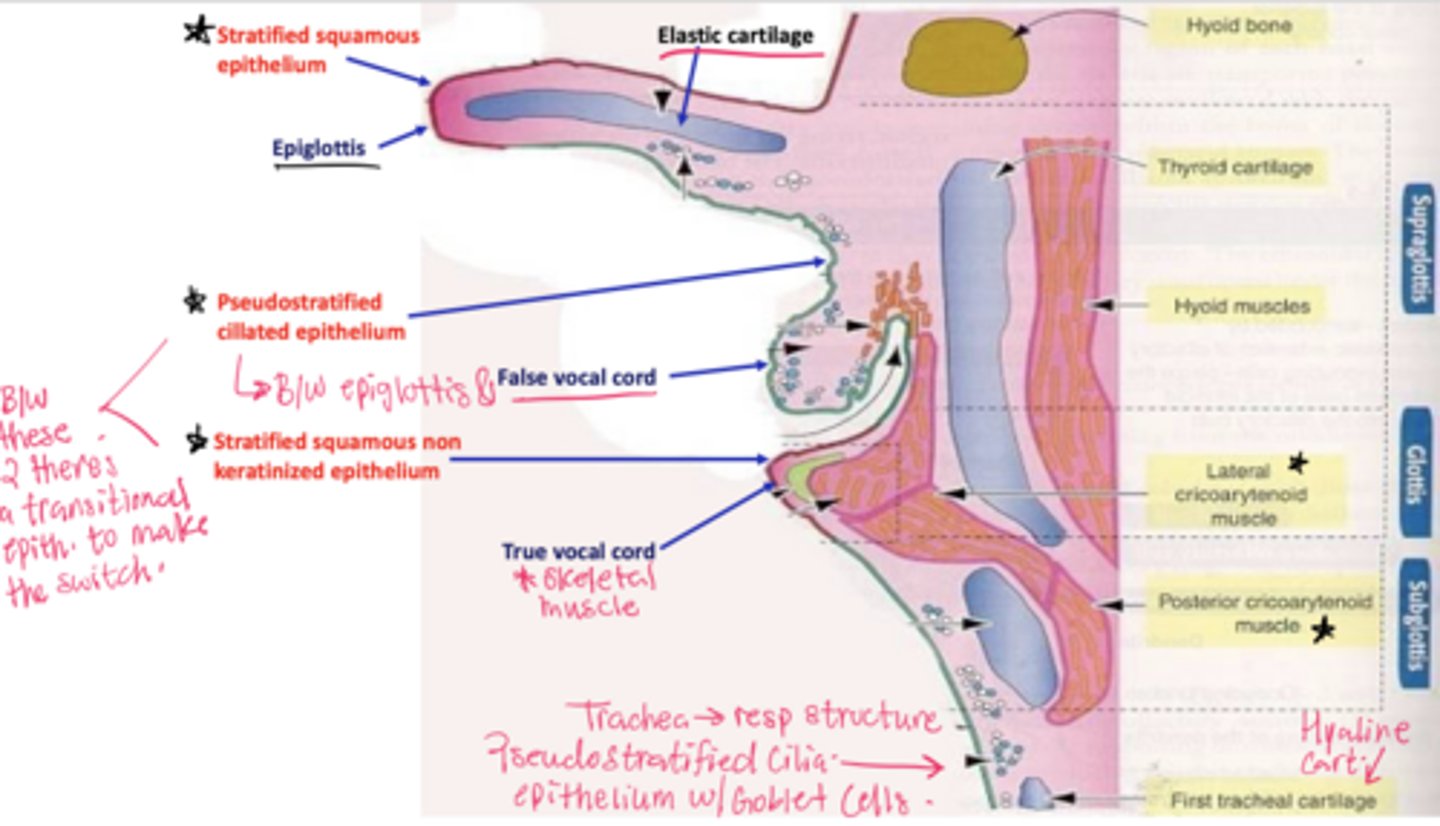

What epithelial transition occurs in the larynx?

Pseudostratified ciliated epithelium -> stratified squamous epithelium (image is at the vestibular folds)

What tissue composes the vestibular folds?

Loose connective tissue with glands and lymphoid aggregations.

What epithelium covers vestibular folds?

Respiratory epithelium.

What muscle is found in the true vocal cords?

Vocalis muscle (skeletal muscle).

What forms the vocal ligament?

A band of elastic fibers.

What epithelium lines the true vocal cords? and why is it this specific epithelium?

Stratified squamous non-keratinized epithelium

so we can speak if we had any other lining the voice will be distorted

Understand how the epithelium changes from epiglottis to treachea`

Epiglottis - stratified squamous epithelium with elastic cartilage

False vocal cords - pseudostra. cillated epithelium

True vocal cords - stratified sq. non keratinized epithelium with skeletal muscle

Trachea - pseudostra. ciliated epithelium with goblet cells (respiratory structure)

Describe the transitional epithelium of the larynx

The main transition occurs near the vocal cords, separating the squamous epithelium of the true vocal cords from the respiratory epithelium pseudostratified ciliated